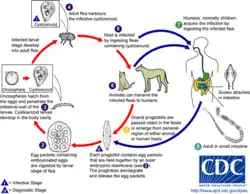

The definitive host within this life cycle is primarily canines, and occasionally felines, and in rare cases young children. The intermediate hosts include fleas (Ctenocephalides spp.) and chewing lice. The first stage in the life cycle is when the gravid proglottids are either passed out through faecal matter, or actively crawl out of the anus of the host. The gravid proglottids once out of the definitive host release eggs. Then, an intermediate host (the larval stage of a flea or chewing louse) will ingest an egg, which develops into a cysticercoid larva. The cysticercoid larva remains viable, but is not infective to carnivores until the flea hatches to an adult and begins feeding on a host (e.g. a dog). Approximately 36 hours after the flea has consumed a blood meal, the infective metacestode develops inside the flea. The metacestode larva must be ingested in a flea by the dog or cat during grooming in order to develop. Humans can also become infected by D. caninum by accidentally ingesting an infected flea. In the small intestine of the definitive host, the metacestode develops into an adult tapeworm, which reaches maturity 4–6 weeks after ingestion. This adult tapeworm produces proglottids, and over time, the proglottids mature and become gravid and eventually detach from the tapeworm and the life cycle starts all over again.[1]